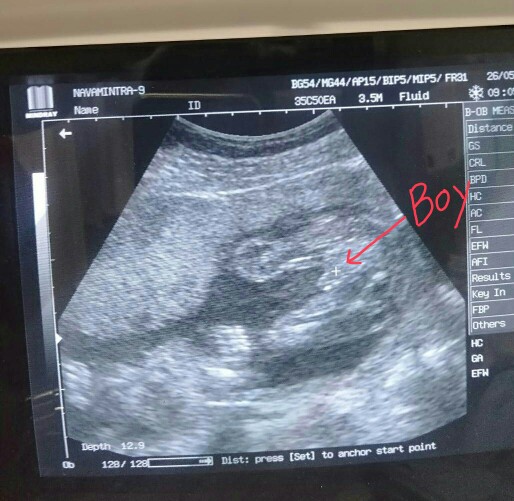

ผช.จ้า ^^

ชายค่ะ